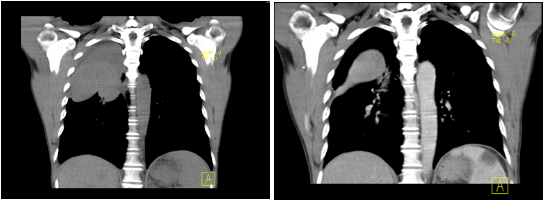

7月28日,金叔来到我院就诊,做胸部CT平扫+增强显示右肺上叶有10.0x8.1x8.0cm大小的软组织肿块影,边界欠清。

随着金叔咯血、咳痰症状明显改善,金叔的第一阶段疗程顺利完成,他也出院回家休养。9月8日他如期回我院复诊,令人高兴的是,他的肿瘤缩小至5.0x4.2x6.4cm,他告诉我们,他很放心也很期待接下来的治疗。

治疗前 治疗后